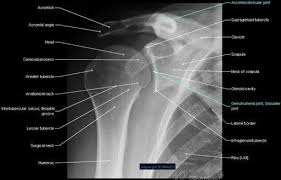

Outline • plain films different views • positioning • interpretation of the plain film. Bones • sternum • clavicles • scapulae • ribs • spine. The medial ends of the clavicles should be equidistant from the spinous process at the level of t4/ t5. Please remove all obscuring objects and, as always, practice proper radiation protection. Assessing the image quality, ripe mnemonic is used;

In this position, the image will clearly show the condition of the. In addition to covering anteroposterior and lateral radiographs, dr. Ahmad explains how to work with a patient in the supine or upright position, as well. Boning up on humerus, clavicle, and ac joint positioning. The position of the patient should be either upright or supine. Getting the most from shoulder positioning. Xray examination of the clavicle radiography of clavicle is routinely done in radiology department in both ap and ap axial projection. Proper positioning for the pelvis and proximal femur the lowdown on lumbar spine positioning radiographic positioning techniques for the cervical spine boning up on humerus, clavicle, and ac joint positioning getting the most from shoulder. Digit imaging requires diligent positioning. Hand, thumb, fingers, wrist, forearm, elbow, humerus, shoulder and clavicle. Additional imaging of the lung apices • properly positioned (not rotated or angulated): Please remove all obscuring objects and, as always, practice proper radiation protection. Bones • sternum • clavicles • scapulae • ribs • spine.